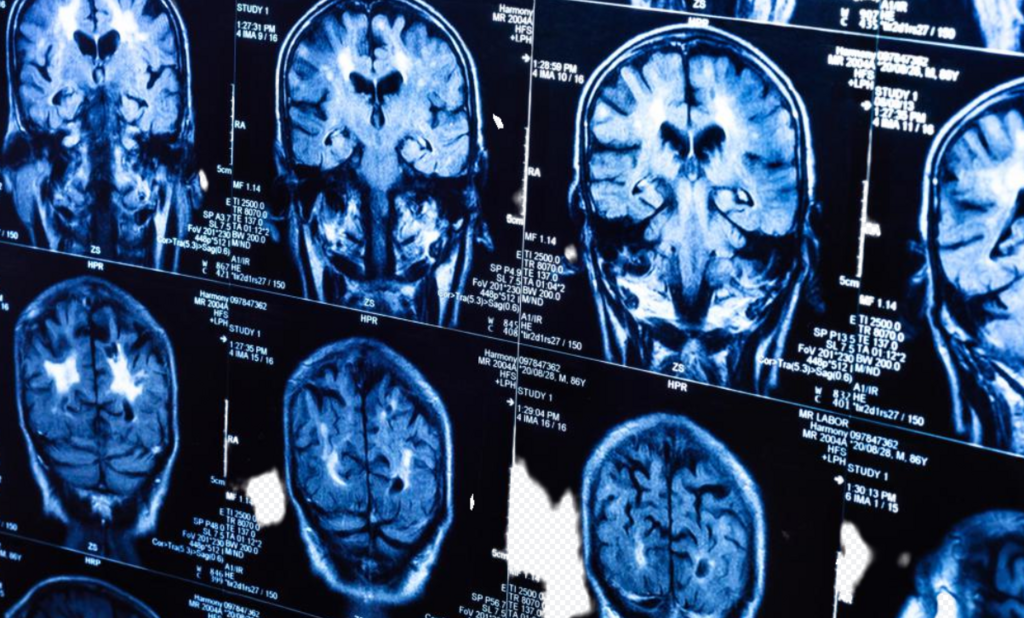

În prezent, îmi desfășor activitatea în cadrul Clinicii Brâncoveanu, un centru medical modern din Craiova, unde pacienții beneficiază de consultații neurologice de specialitate și investigații avansate: